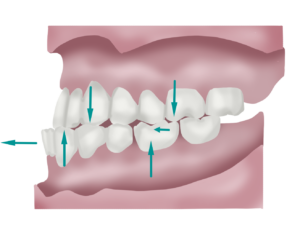

Classe III Molar

En la classe III molar trobem una mandíbula excessivament avançada respecte el maxil·lar. També prenem els primers molars definitius com a punt de referència per avaluar la complexitat del cas.

En el cas de les maloclusions de classe III trobem una llengua baixa amb deglució atípica, prognatisme mandibular i un augment de les curvatures vertebrals, provocant també una síndrome de disfunció postural descendent, en aquest cas amb altres particularitats, però donant el mateix resultat que seria el de requerir un esforç extra al cos per a treballar i generar tensions i dolors innecessaris.

Estèticament també poden suposar un problema les maloclusions per avançament mandibular, degut a una mandíbula molt prominent que pot inclús modificar la fesomia de l’individual llarg dels anys.

En la classe III podem trobar dos tipus de mossegada segons la causa que l’ha originat:

*Classe III amb mossegada oberta: les dents de dalt no contacten amb les de baix quan tanquem la boca, queda un espai obert al davant. És perquè la llengua es col·loca sempre entre les dents superiors i les inferiors a l’hora d’empassar i en alguns casos també a l’hora de parlar.

*Classe III amb sobremossegada: les dents de baix recobreixen per davant a les de dalt, en aquests casos trobem una gran rigidesa muscular i, quan es detecta a l’edat adulta, dolors crònics.